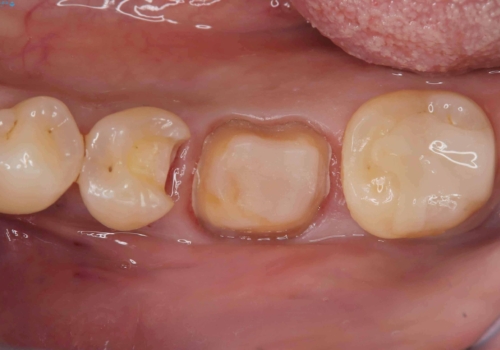

- 銀歯2本の下が虫歯になっていたので、フルジルコニアクラウンとセラミックインレーで治療を行いました。

適合が良い被せ物を入れるために、歯の境としっかり合わせた仮歯を入れ、歯茎の状態を良くしてからシリコンで型取りをしています。